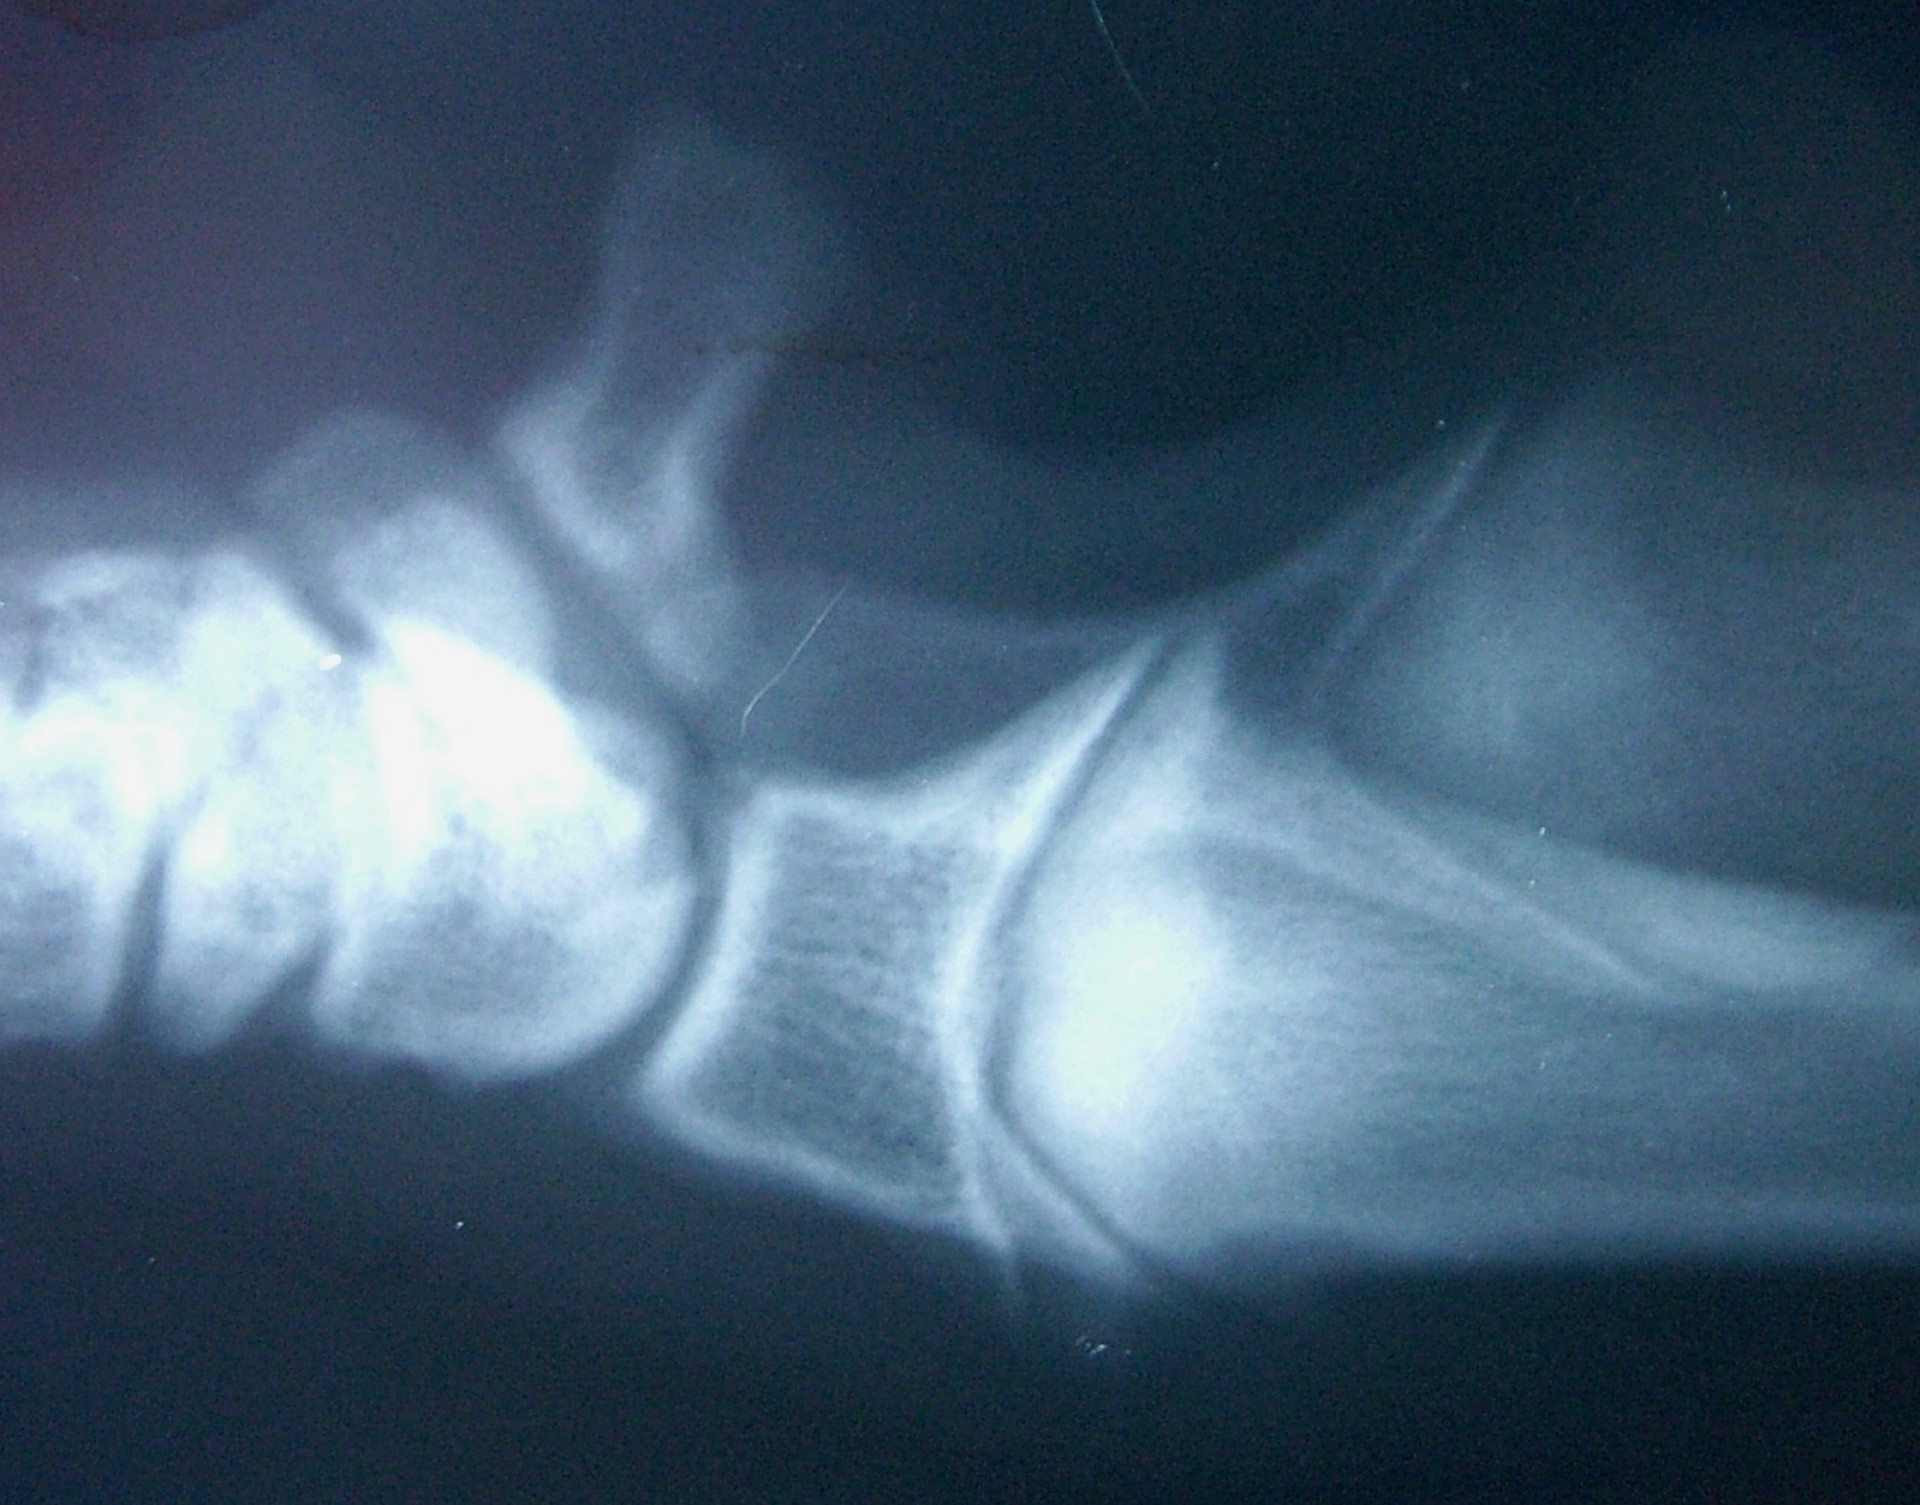

Az alkarcsont növekedési zónájának záródása (short radius)

Az alkarcsont növekedési zónájának záródása általában a könyökízületben un.: inkongruenciát okoz. A könyökízület működéséhez az azt alkotó 3 csont (karcsont, könyökcsont, alkarcsont) tökéletes illeszkedése elengedhetetlen. Azokban az esetekben amikor bármely 2, a könyökízület alkotásában résztvevő csont ízületi felszíne nem illeszkedik tökéletesen,rendellenes ízületi alakulásról, inkongruenciáról beszélünk. Ezekben az esetekben az ízületi felszínek nem megfelelő terhelődése azok kopásához, idült ízületgyulladáshoz, következményesen fájdalomhoz vezet.

Az alkarcsont alsó vagy felső növekedési zónájának lezáródása esetén a könyökízületben kialakuló inkongruencia az ízület mozgásának fájdalmasságához, a mozgáspálya beszűküléséhez vezet. Paradox módon az ilyen elváltozás esetén is (mivel az alkarcsont a teherviselő csont) a könyökcsont osteotomiájával, annak növekedésének korlátozásával gyógyítjuk a beteget.